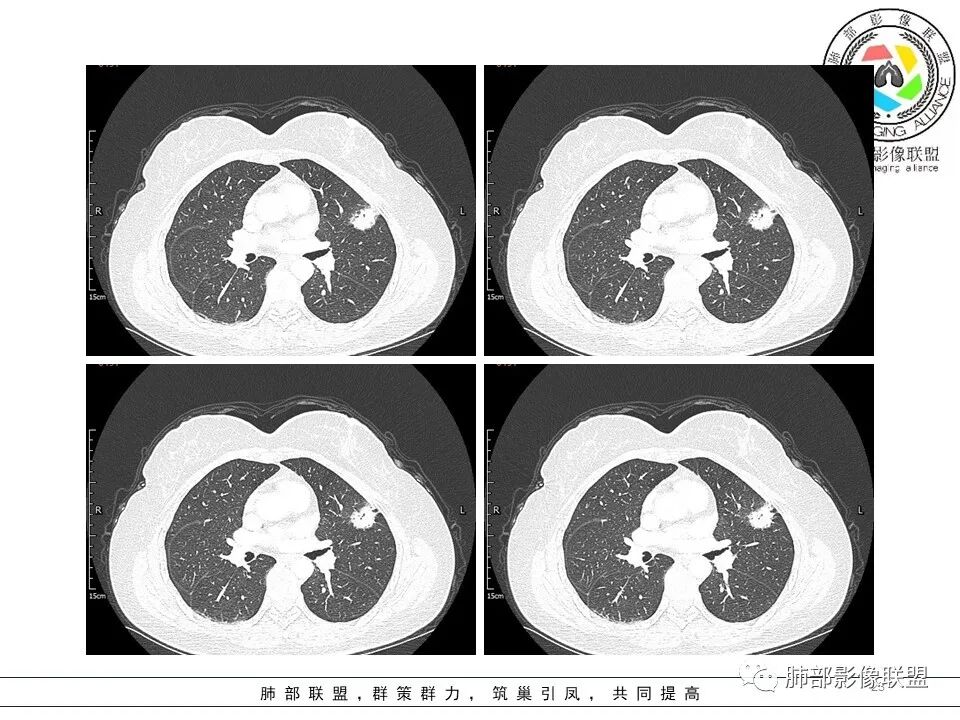

左肺上叶胸膜下不规则结节影,分叶、粗短毛刺,胸膜牵拉等,像个“刺头”。

1.病灶周围向几个方向膨出的边界清楚的磨玻璃影,这些磨玻璃影时隔几个月依然,几乎可以排除出血及一般的炎性改变。

2.病灶的胸膜牵拉线与其间病灶胸膜侧的磨玻璃边构成朝向胸壁的“月牙铲”结构,这种影像学表现某种程度上反映出病理学特征——病灶收缩+小叶间隔阻挡。

3.病灶实性密度区强化明显,这有助于我们区分一些其他类似病灶,如结核灶等!

结合临床,应当高度怀疑浸润性肺腺癌!

在影像上观察到肿块或磨玻璃结节一侧的内凹,像个月牙铲形态,病理是肿瘤生长受到小叶间隔阻挡并受肿瘤内部的收缩力形成,王兆宇老师称之为“月牙铲”!对诊断肺腺癌较有特异性。